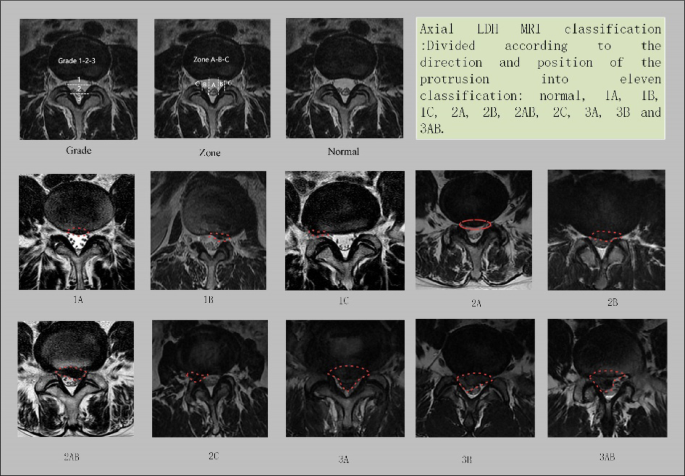

Final diagnostic categories included Normal, 1 A/B/C, 2 A/B/AB/C, and 3 A/B/AB (Fig. 2). Discrepancies were resolved via consensus review. The categories labeling protocol was derived from the prospective study by Mysliwiec LW et al.13 on LDH management.

LDH classification diagram. LDH, lumbar disc herniation; MRI, magnetic resonance images.